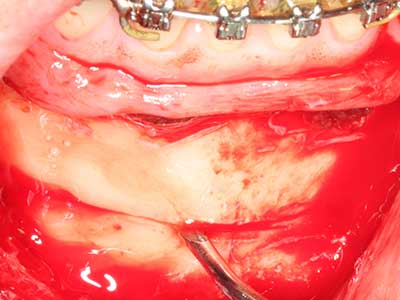

La preparación de la ventana lateral en la elevación del suelo del seno maxilar representa un enorme reto, sobre todo para profesionales de la implantalogía que tienen poca experiencia en técnicas quirúrgicas. Retirar la cobertura ósea del seno maxilar sin provocar daños en la membrana de Schneider es tan solo una parte de la operación; tras crear un acceso suficiente, es preciso movilizar con cuidado la mucosa del seno maxilar a fin de dejar espacio para el material o los implantes que vayan a incorporarse. En esta aplicación la cirugía piezoeléctrica resulta útil en dos sentidos: por un lado, el uso de insertos diamantados permite realizar una retirada selectiva del hueso y, si se actúa con cuidado, la membrana permanece intacta, y por otro lado, las frecuencias de ultrasonidos favorecen también un desprendimiento sin problemas de la membrana, pues se transfieren al espacio comprendido entre la mucosa y el suelo del seno maxilar gracias al uso de piezas romas especiales (Cassetta, Ricci et al. 2012, Pereira, Gealh et al. 2014) (Rickert, Vissink et al. 2013). De este modo, no es de extrañar los trabajos publicados en la actualidad sobre la técnica de elevación del suelo del seno maxilar mediante la técnica de Caldwell-Luc con instrumentos piezoeléctricos (Wallace, Tarnow et al. 2012).